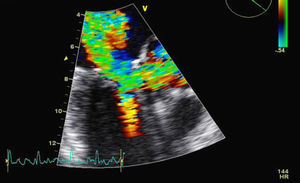

The patient was admitted for decompensated heart failure. Transthoracic echocardiography (TTE) performed on the first day of hospitalization (with HR 120–150bpm) (Figure 1) revealed aortic valve fibrosis with no restriction of opening, together with mild regurgitation.

The MV presented fibrocalcification, with increased echogenicity of the annulus; the anterior leaflet and subvalvular apparatus were obstructing the LVOT, resulting in an intraventricular gradient of 110mmHg and moderate paroxysmal regurgitation (probably related to the intermittent nature of the LVOT obstruction). The left atrium was severely dilated (6.1cm), and the left ventricle was hypertrophied (diastolic diameter 4.3cm) but with good global systolic function. The right chambers were of normal size, with pulmonary artery pressure estimated at 40mmHg.